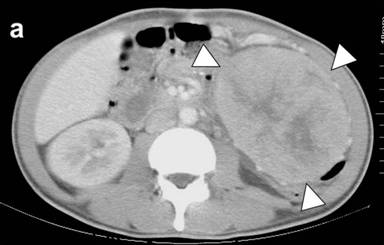

A Japanese man at age of 43 years attended at our hospital, complaining of severe general fatigue and weight loss of 10 kg in the last 3 months. He had more than 10 times movements of watery diarrhea a day. He was severely dehydrated, and blood urea nitrogen (BUN) and creatinine levels were increased to 211 mg/dL (reference range: 8-20 mg/dL) and 3.80 mg/dL (reference range: 0.61-1.04 mg/dL), respectively. With institutional treatment of hydration and correction of electrolytes, systemic examination was done. A large mass was palpable in the left upper abdomen, and CT demonstrated a wrist-sized tumor in the tail of the pancreas (Figure 1a). The serum K+ level was slightly decreased at 2.8 mEq/L (reference range: 3.5-5.0 mEq/L) and Ca2+ was 9.3 mg/dL (reference range: 8.4-10.4 mg/dL). Tumor markers such as alpha-fetoprotein (AFP), CEA and CA 19-9 were within the normal range. The blood levels of VIP and calcitonin were increased to 649 pg/mL (reference range: 0-100 pg/mL) and 66,700 pg/mL (reference range: 15-86 pg/mL), respectively. The glucagon level was slightly elevated, and other hormone levels were in normal range. There was no palpable nodule in the thyroid or neck region. CT and MRI detected no other tumor except the pancreatic tumor, and the accumulation of 18F-fluorodeoxy-glucose was detected only in the pancreas by PET. On day 5 after the admission, intracutaneous injection of octreotide was started at a dose of 100 μg/day, and on day 10 the dose was increased to 200 μg/day. The bowel movement was reduced, and general condition was improved. On day 33, the patient underwent pancreaticosplenectomy and partial resection of the transverse colon.

Figure 1. CT scan image of the abdomen. a. Large tumor was found at the tail of the pancreas (arrow heads). The CT scan of the liver 19 months (b.) and 25 months (c.) after the operation. Arrowheads indicate one of the metastatic tumors. The size appeared unchanged at 25 months. |